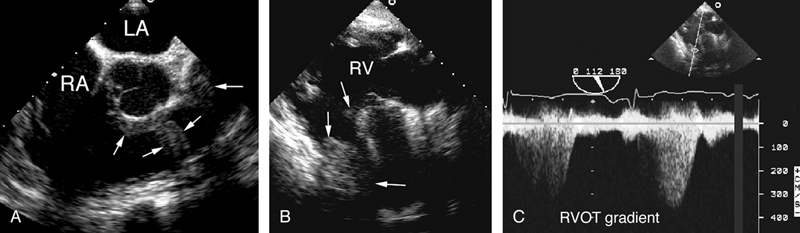

فحوصات تشخيصية لبعض امراض القلب والشرايين التاجية